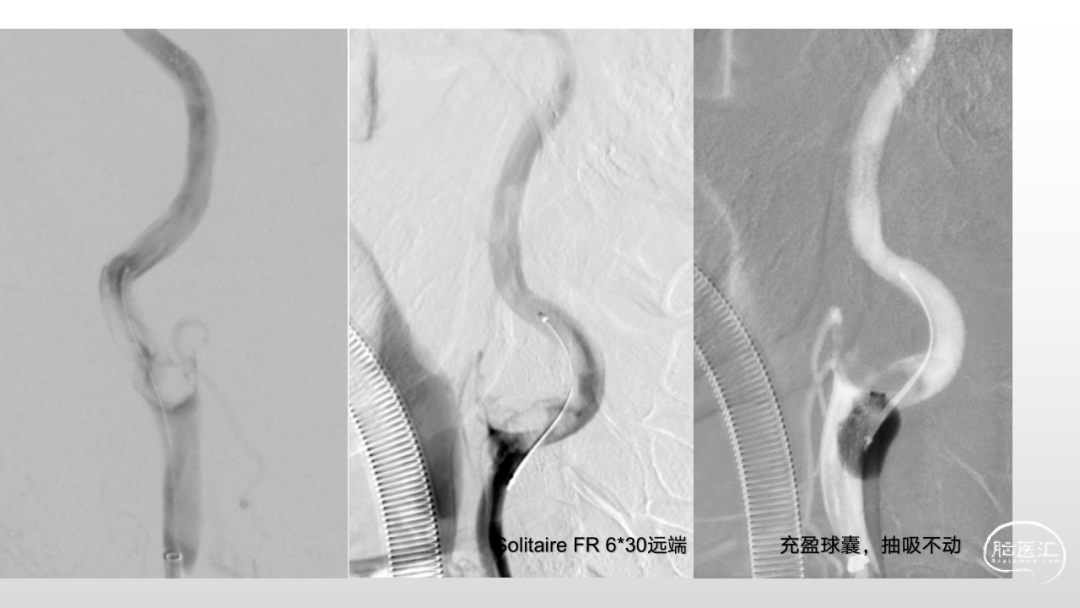

取之有道·第54期|李子付:Flowgate2取栓应用